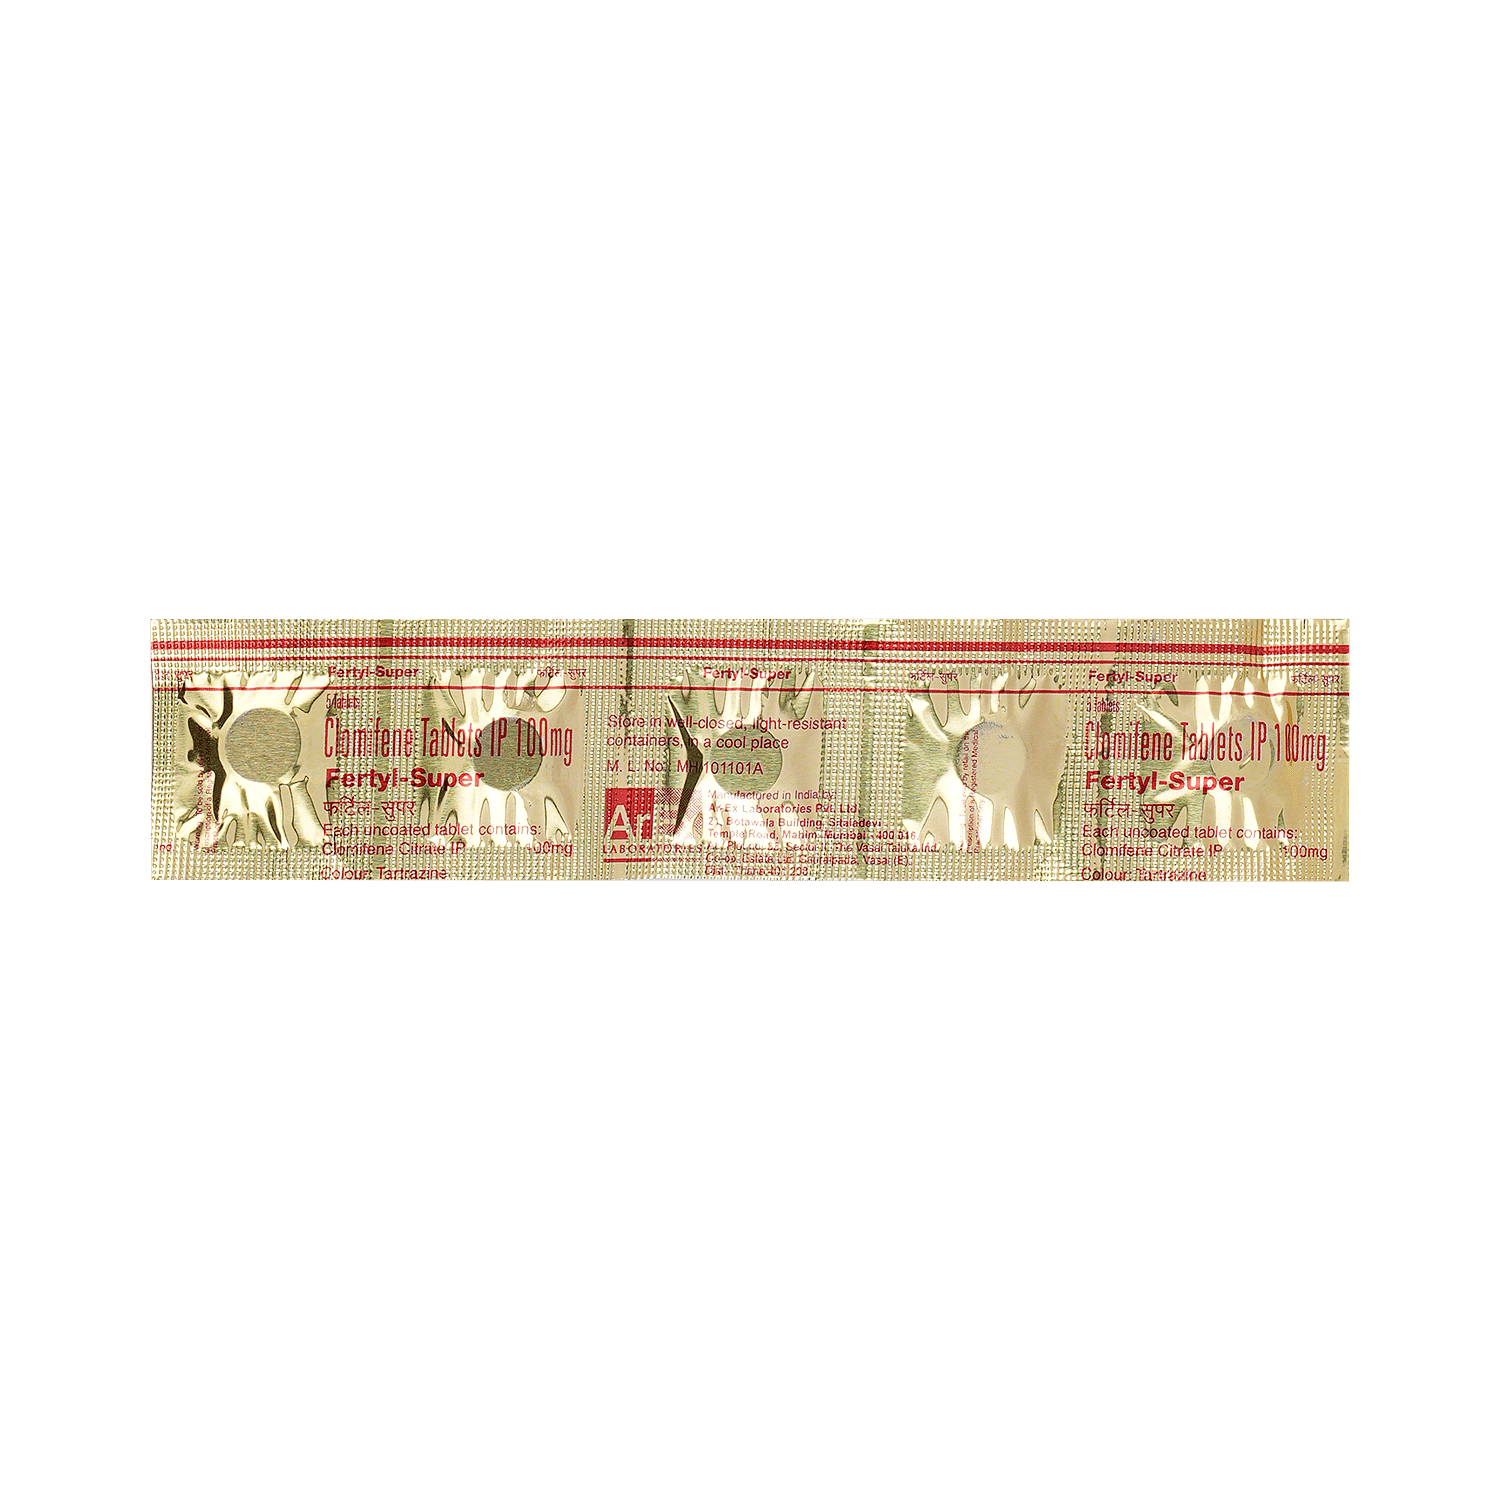

Salt Composition

Clomiphene (100mg)

Dosage Form

Tablet